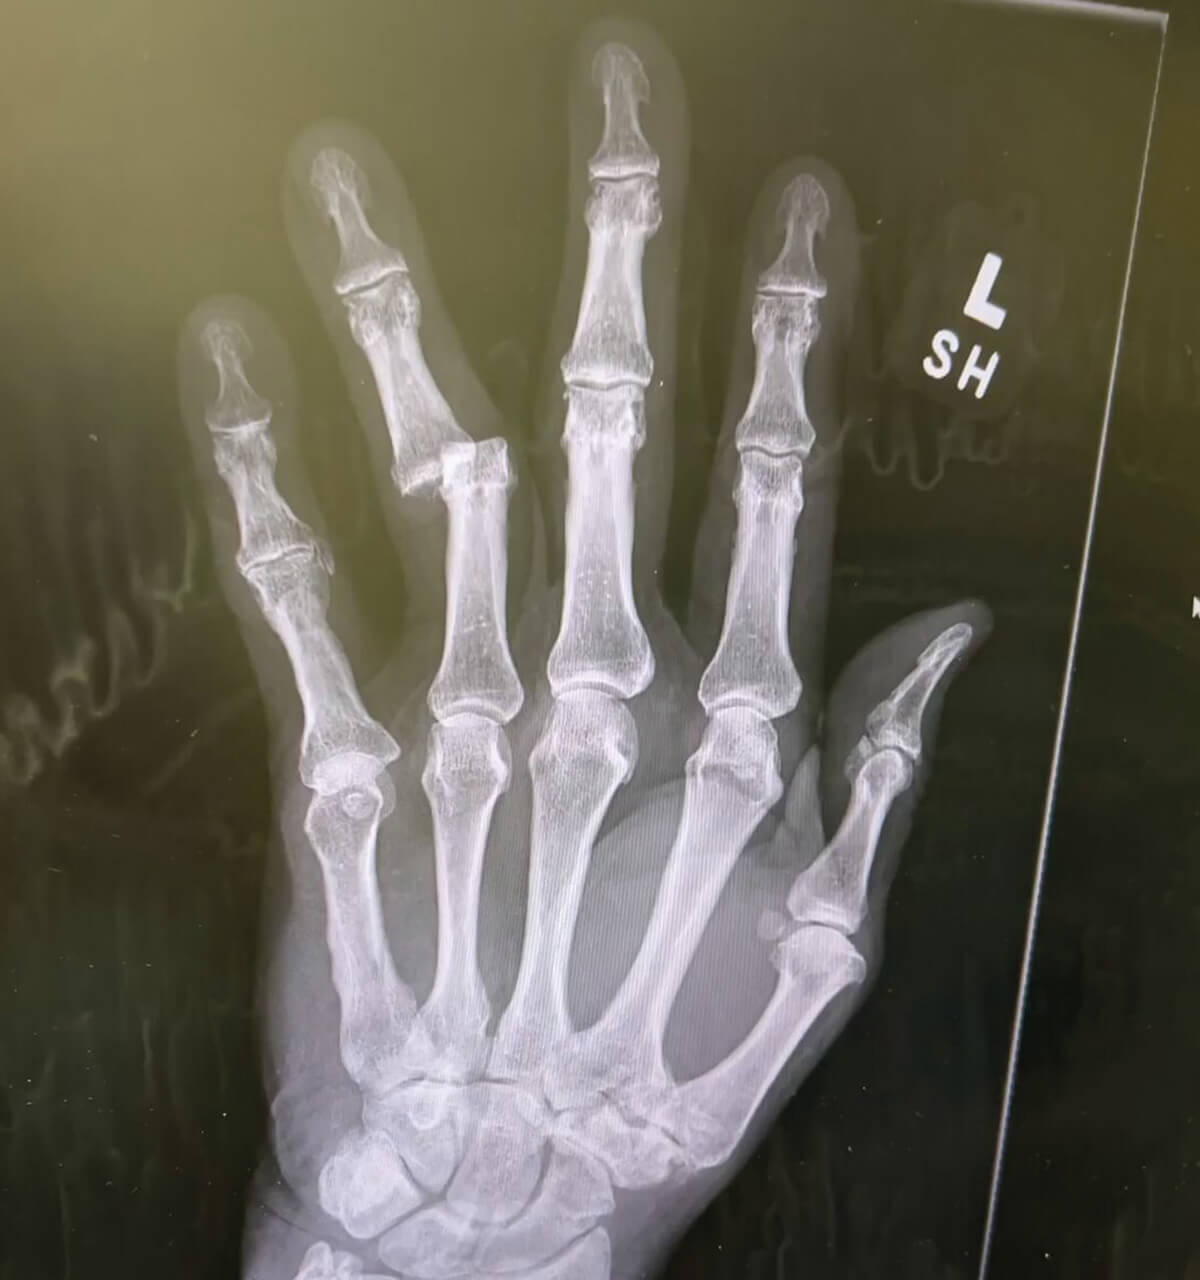

Figure 2: Xray showing fracture dislocation of PIP joint LD4.